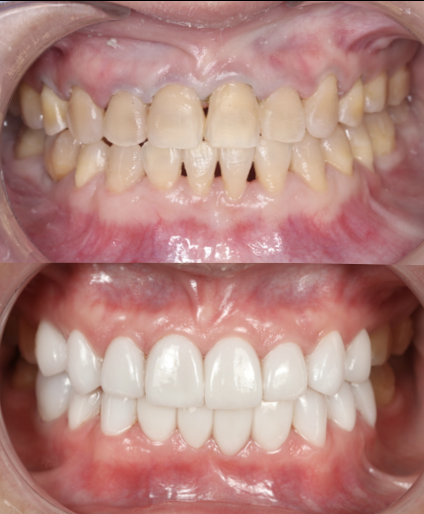

BRACES - SEVERE CROWDING

This patient had severe dental crowding with overlapping and rotated teeth that affected both smile aesthetics and bite function. Through comprehensive orthodontic treatment with braces performed by the Moral Dental Clinic team, the teeth were carefully aligned, arch form restored, and bite improved. The final result shows a beautiful, balanced smile with better oral function, easier cleaning, and long-term stability